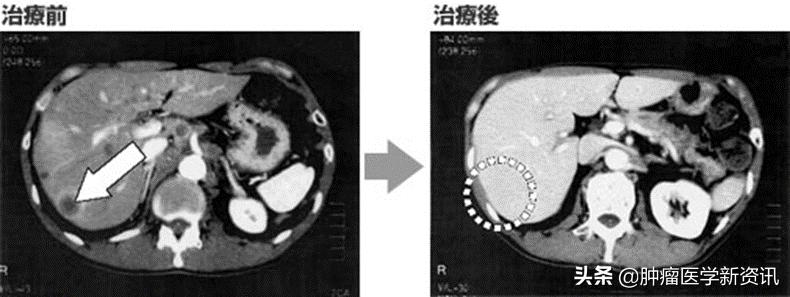

1. 一位60岁的女性被诊断为4a期胰腺癌。由于胰腺癌累及周围的大血管而无法手术,因此进行化疗,然而预后不佳。于是患者接受了日本免疫细胞疗法与化疗相结合的联合治疗,肿瘤标志物CA19-9稳定下降,且在治疗后6个月CT显示肿瘤缩小到几乎看不见的程度。后来患者又接受了日本免疫细胞疗法与放射治疗、化疗的联合疗法,使肿瘤缩小到可以进行手术的状态,并手术摘除肿瘤。对患者进行随访,手术后5年癌症都没有复发迹象,患者情况良好(如下图)。